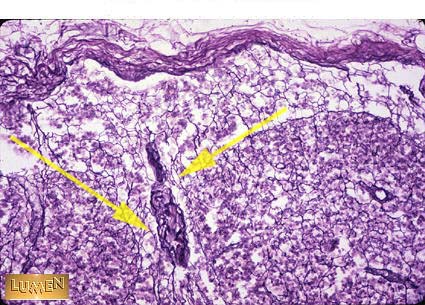

Trabecula of Lymph Node